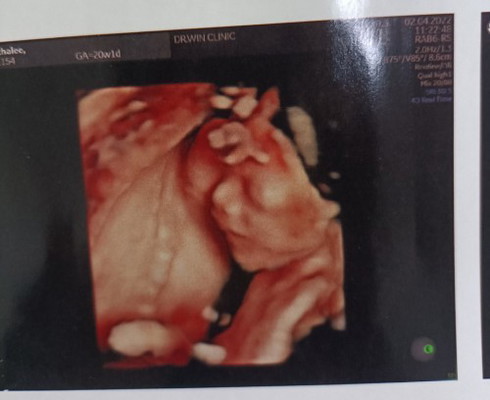

#คุณแม่ๆช่วยแนะนำหน่อยค่ะ กินนมยี่ห้อไหนน้ำหนักถึงจะขึ้นคะ ก่อนท้อง นน.42 แพ้ท้อง นน.ลดเหลือ38 ตอนนี้20W1Dแร้ว นน.41เองคะ #ขอบคุณล่วงหน้านะคะ

329กรัมคะ